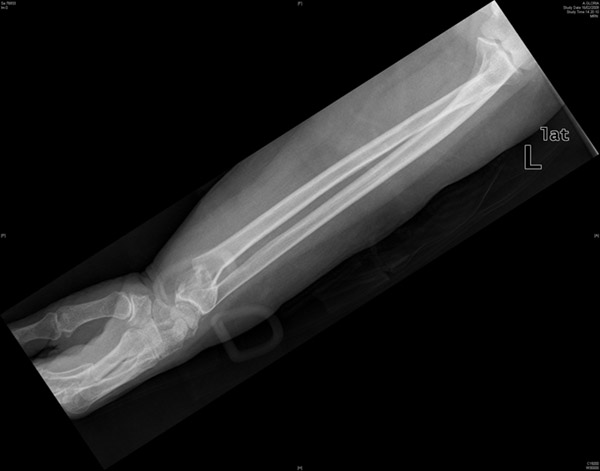

Deformidad de cúbito tras fracturas acumuladas

Deformidad de cúbito. fracturas acumuladas.